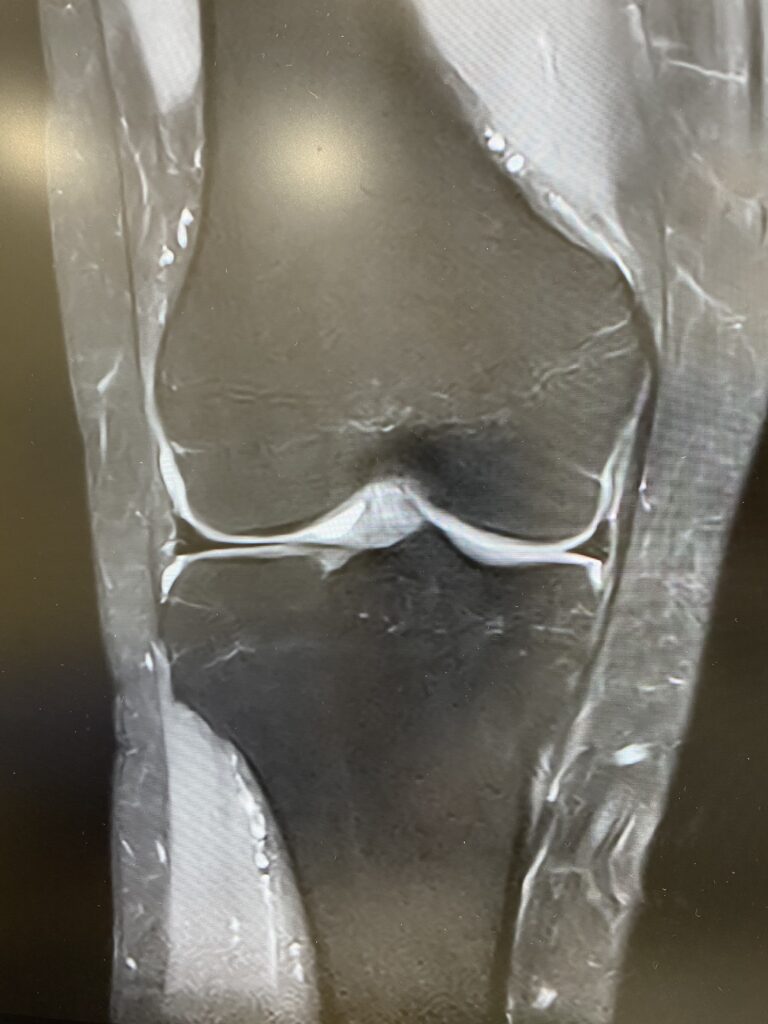

1.5T MRIへの更新作業が完了しました。

9月上旬から休止していたMRIの撮影が可能となり、画像精度が飛躍的に向上します。